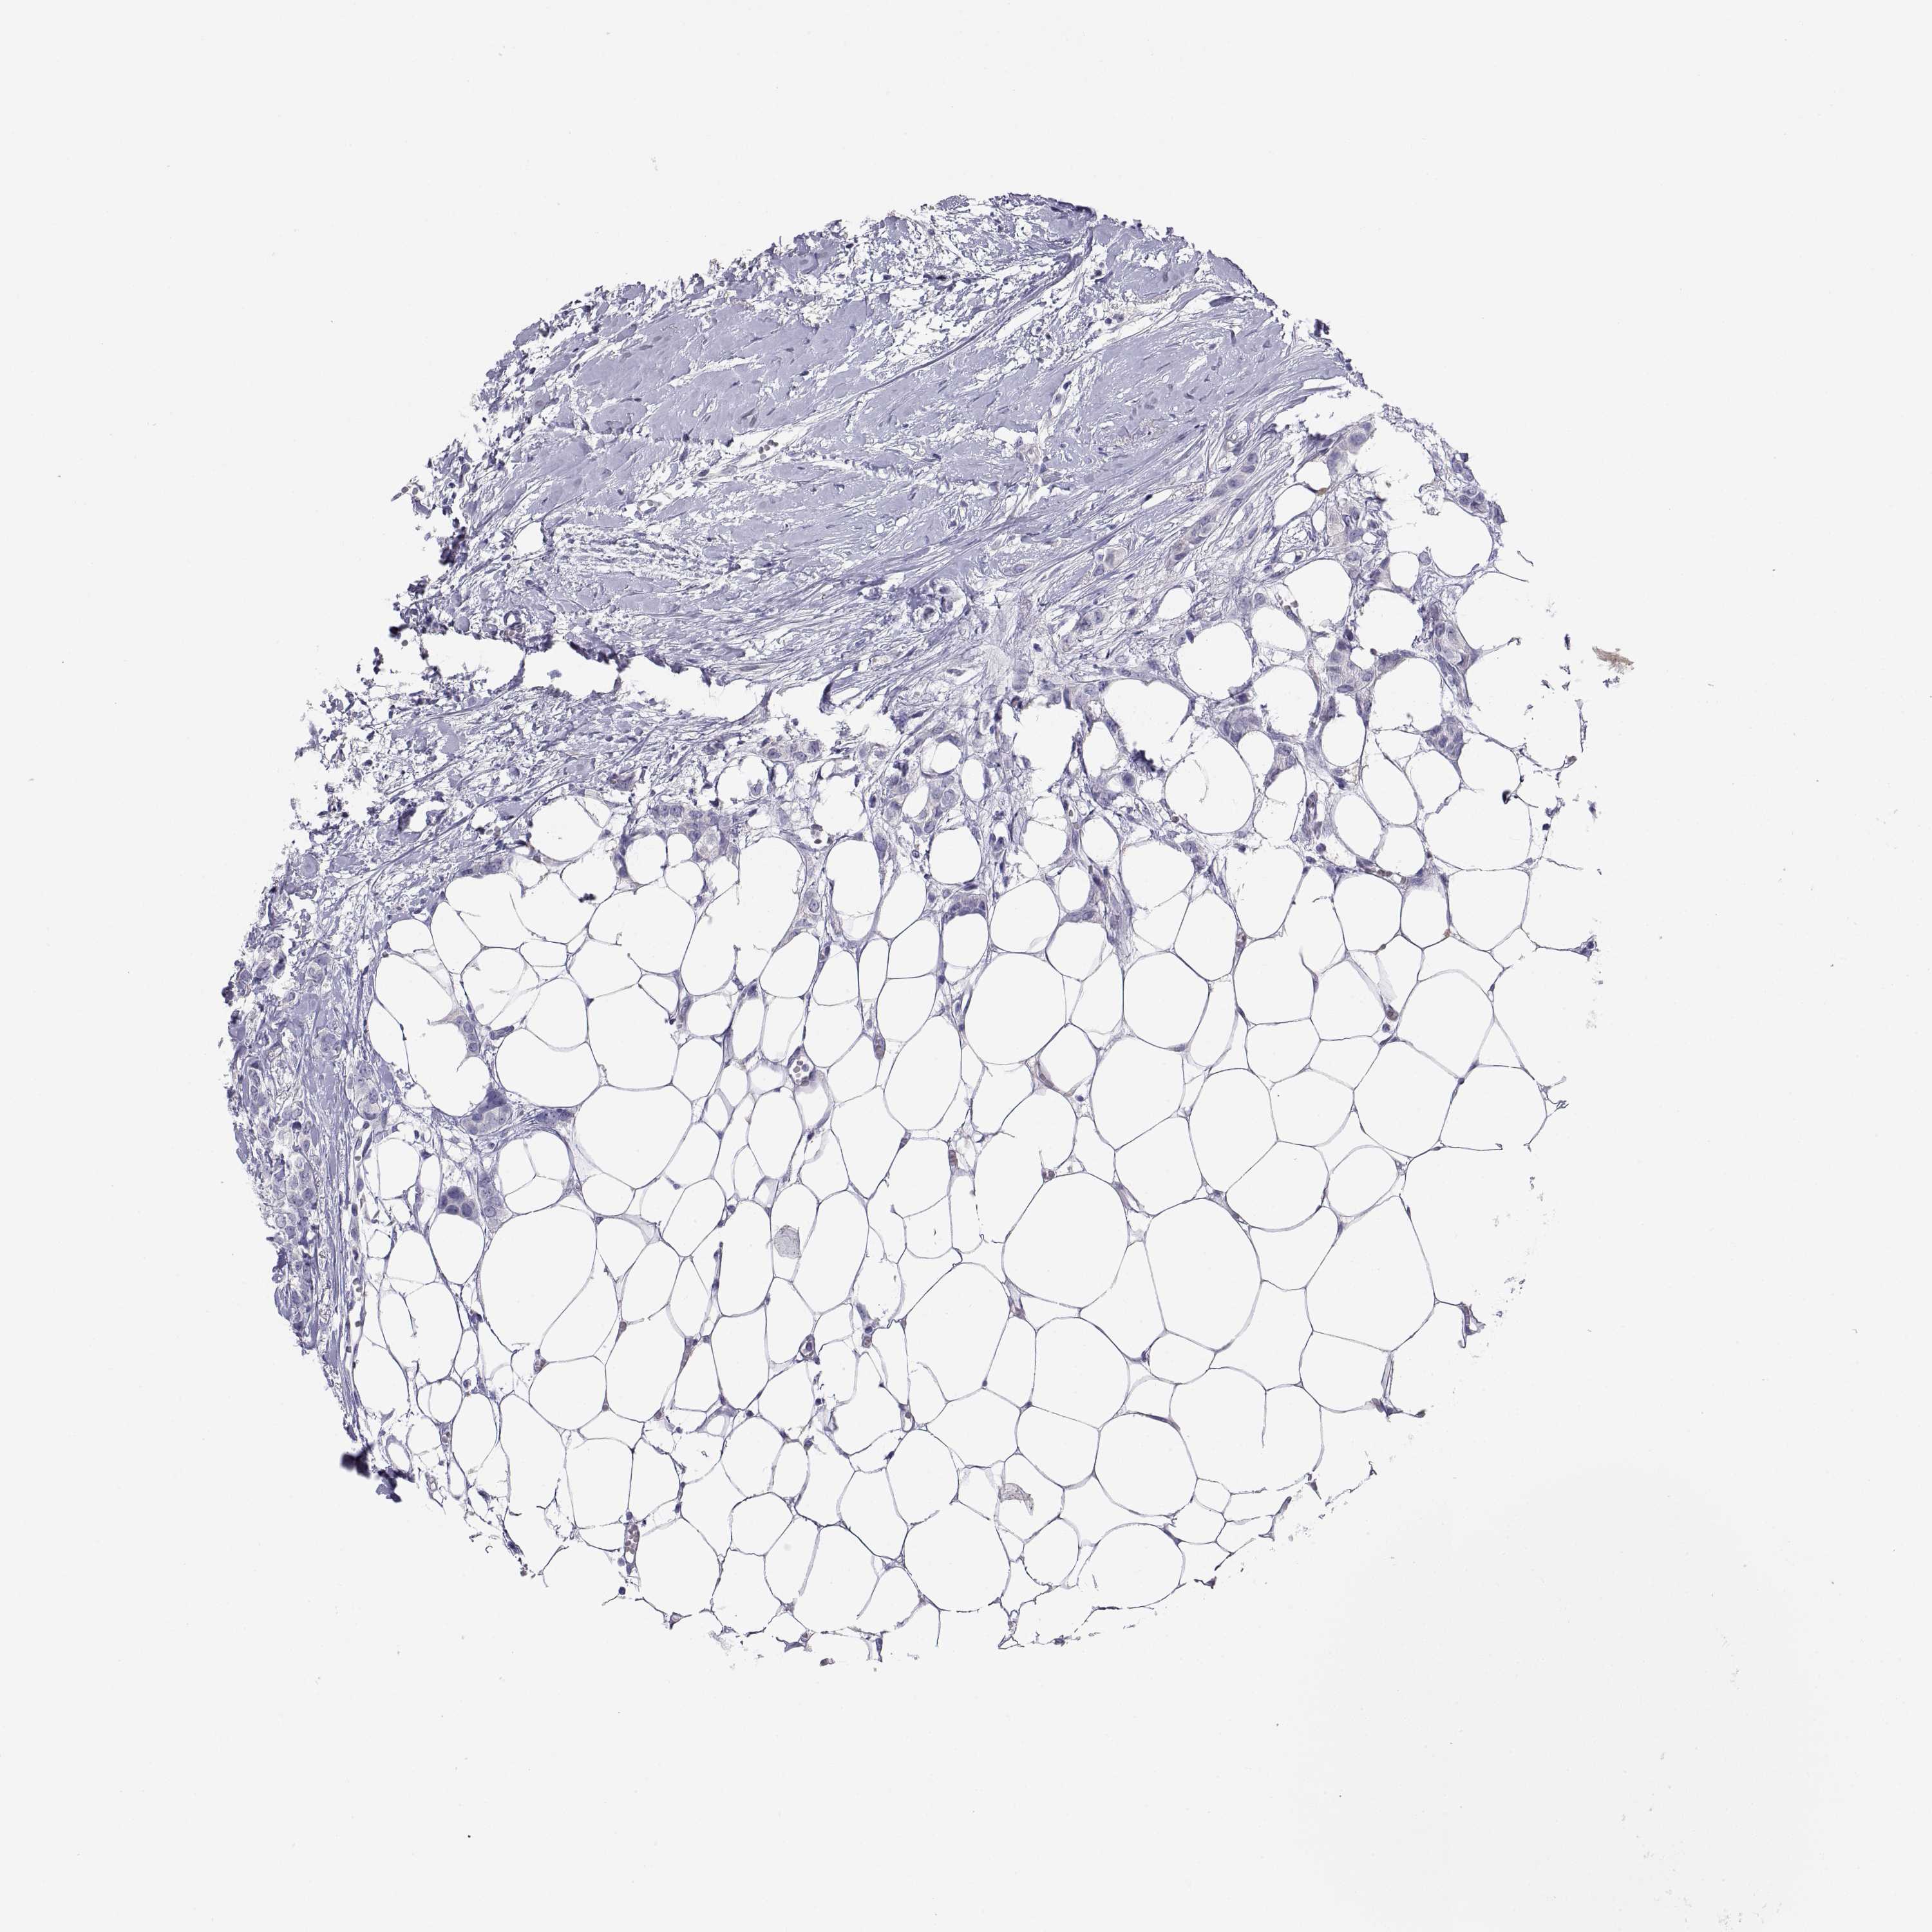

Breast cancer

Human cancer